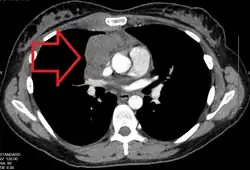

Diagram showing common sites where lymphoma spreads

After a diagnosis and before treatment, a cancer is staged. This refers to determining if the cancer has spread, and if so, whether locally or to distant sites. Staging is reported as a grade between I (confined) and IV (spread). The stage of a lymphoma helps predict a patient's prognosis and is used to help select the appropriate therapy.[43]

The Ann Arbor staging system is routinely used for staging of both HL and NHL. In this staging system, I represents localized disease contained within a lymph node group, II represents the presence of lymphoma in two or more lymph nodes groups, III represents spread of the lymphoma to lymph nodes groups on both sides of the diaphragm, and IV indicates spread to tissue outside the lymphatic system. Different suffixes imply involvement of different organs, for example S for the spleen and H for the liver. Extra-lymphatic involvement is expressed with the letter E. In addition, the presence of B symptoms (one or more of the following: unintentional loss of 10% body weight in the last 6 months, night sweats, or persistent fever of 38 °C or more) or their absence is expressed with B or A, respectively.[44]

CT scan or PET scan imaging modalities are used to stage a cancer. PET scanning is advised for fluorodeoxyglucose-avid lymphomas, such as Hodgkin lymphoma, as a staging tool that can even replace bone marrow biopsy. For other lymphomas, CT scanning is recommended for staging.[43]